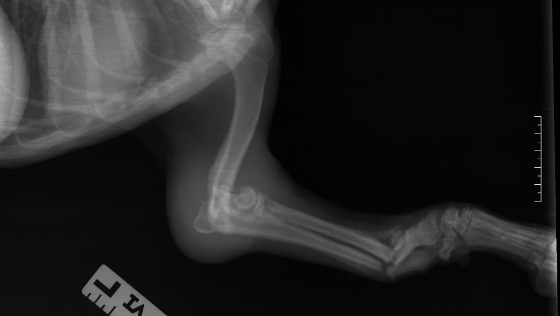

Sheldon. czeka na dom, potrzebuje wsparcia

Sheldon Wspaniały :)

Sheldon bardzo dziękuje. Aktualnie jeszcze jest w klinice